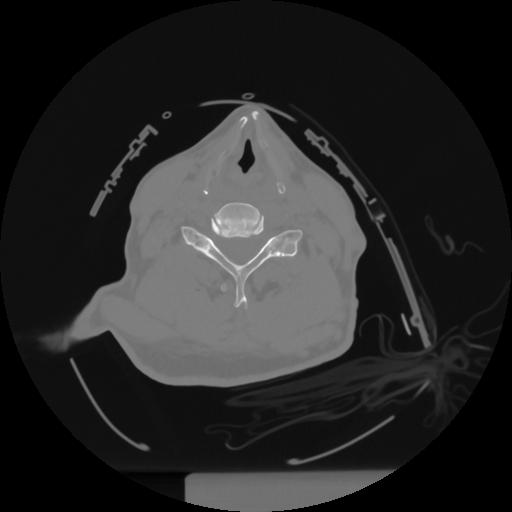

12 P.BLANDAS,,Vol,0.5,P.BLANDAS,,